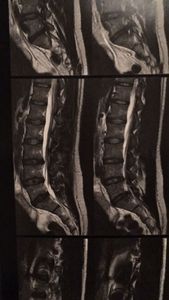

Venho compartilhar brevemente meus desafios de saúde e a importância do seu apoio. Fui diagnosticado com hérnia de disco e compressão do nervo ciático, condições que têm afetado minha qualidade de vida.

Esses problemas causam dores intensas e limitações físicas significativas, impossibilitando-me de trabalhar há quase um ano. Infelizmente, minha situação financeira não permite que eu custeie a fisioterapia necessária para minha recuperação.

Os médicos me recomendaram a fisioterapia como tratamento ideal para fortalecer os músculos do core, consequentemente, reduzir a dor causada pela hérnia de disco que comprime o nervo ciático. Com o apoio financeiro recebido, poderei iniciar as sessões de fisio que trará alívio e permitirá uma maior qualidade de vida.